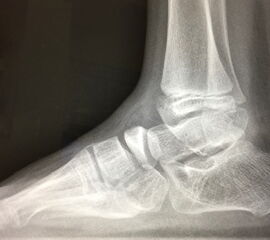

Abb.1 a-b: Beispiel einer noch offenen Wachstumsfuge im dorsalen Bereich des Calcaneus: (a) Alter 6 und (b) Alter 9 Jahre.

In der Regel bestehen aktive Wachstumsfugen bei Mädchen bis zum 12. und bei Jungen bis zum 14. Lebensjahr, mit Abweichungen von einem Jahr nach unten und nach oben. Präzise Informationen unter anderem darüber gibt das präoperative Röntgenbild (Abb. 2).